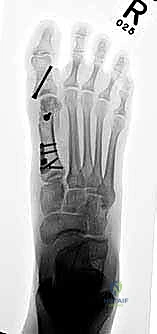

- يتم تحديد مواقع المسامير أو الشرائح المعدنية من الجراحة السابقة وإزالتها (Hardware Removal). قد تكون هذه الخطوة صعبة إذا نما العظم فوق المسامير.

أ. إعادة القطع العظمي (Revision Osteotomy - Scarf or Chevron)

إذا كان الفشل ناتجًا عن تصحيح غير كافٍ في الجراحة الأولى، وكان المفصل لا يزال سليمًا (لا توجد خشونة شديدة)، يقوم الدكتور هطيف بإجراء قطع عظمي جديد (مثل تقنية Scarf أو Chevron) لإعادة توجيه العظم وتثبيته بمسامير تيتانيوم حديثة لا تسبب تهيجًا.

إذا كان سبب التكرار هو "فرط الحركة" في مفصل منتصف القدم (TMTJ)، فإن الحل الوحيد لمنع التكرار المستقبلي هو دمج (إيثاق) هذا المفصل. يزيل الدكتور هطيف الغضروف من المفصل، يصحح زاوية العظم، ويثبته بشريحة معدنية قوية ومسامير حتى يلتحم العظمان معًا. هذه العملية تعالج أصل المشكلة من الجذور.

في هذه العملية، يتم إزالة الغضروف التالف من مفصل الإصبع الكبير، ودمج العظام معًا في وضع مستقيم قليلاً للأعلى للسماح بالمشي الطبيعي. يتم التثبيت باستخدام شريحة ومسامير متقاطعة. النتيجة هي إصبع مستقيم، خالٍ تمامًا من الألم، ولا يمكن أن يعود للتشوه أبدًا.